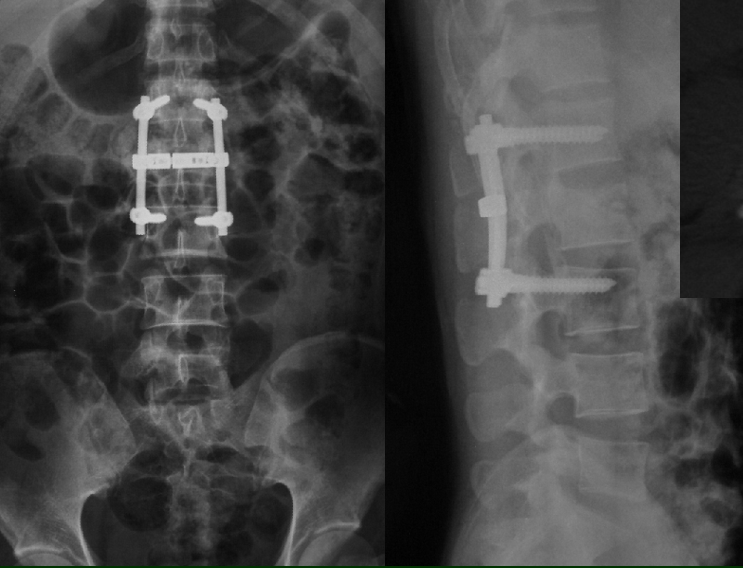

L4三柱爆裂骨折

SSE+MacsTL

L1,Moss- Miami

术后半年,隐约可见钛网下陷

术后1年,钛网下陷、松动,钢板也明显松动。

翻修后的X线表现